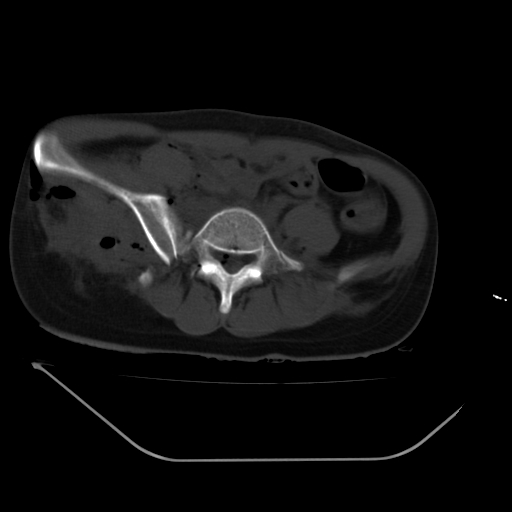

以下是引用liuyue在2008-7-19 13:02:00的发言:[br]1.肝右叶后下段及右肾挫裂伤伴腹腔积血。[br]2.右侧多发性肋骨骨折、横突骨折、右髂骨骨折伴周围软组织挫伤。[br]3.右侧腰大肌肿胀,并可见低密度影,如为气体,则肠道挫裂伤待除外。

以下是引用zhengfaming在2008-7-19 14:42:00的发言:[br]1.肝右叶后下段及右肾挫裂伤伴腹腔积血。脾脏挫裂伤待排[br]2.右侧多发性肋骨骨折、横突骨折、右髂骨骨折伴周围软组织挫伤。[br]3.右侧腰大肌肿胀,并可见低密度影,如为气体,则肠道挫裂伤待除外

以下是引用道哥在2008-7-19 16:52:00的发言:[br]肝右叶后下段及右肾挫裂伤、脾破裂伴腹腔积血。[br]2.双侧多发性肋骨骨折、横突骨折、右髂骨骨折伴周围软组织挫伤。[br]3.右侧腰大肌肿胀,并可见低密度影,如为气体,则肠道挫裂伤待除外。